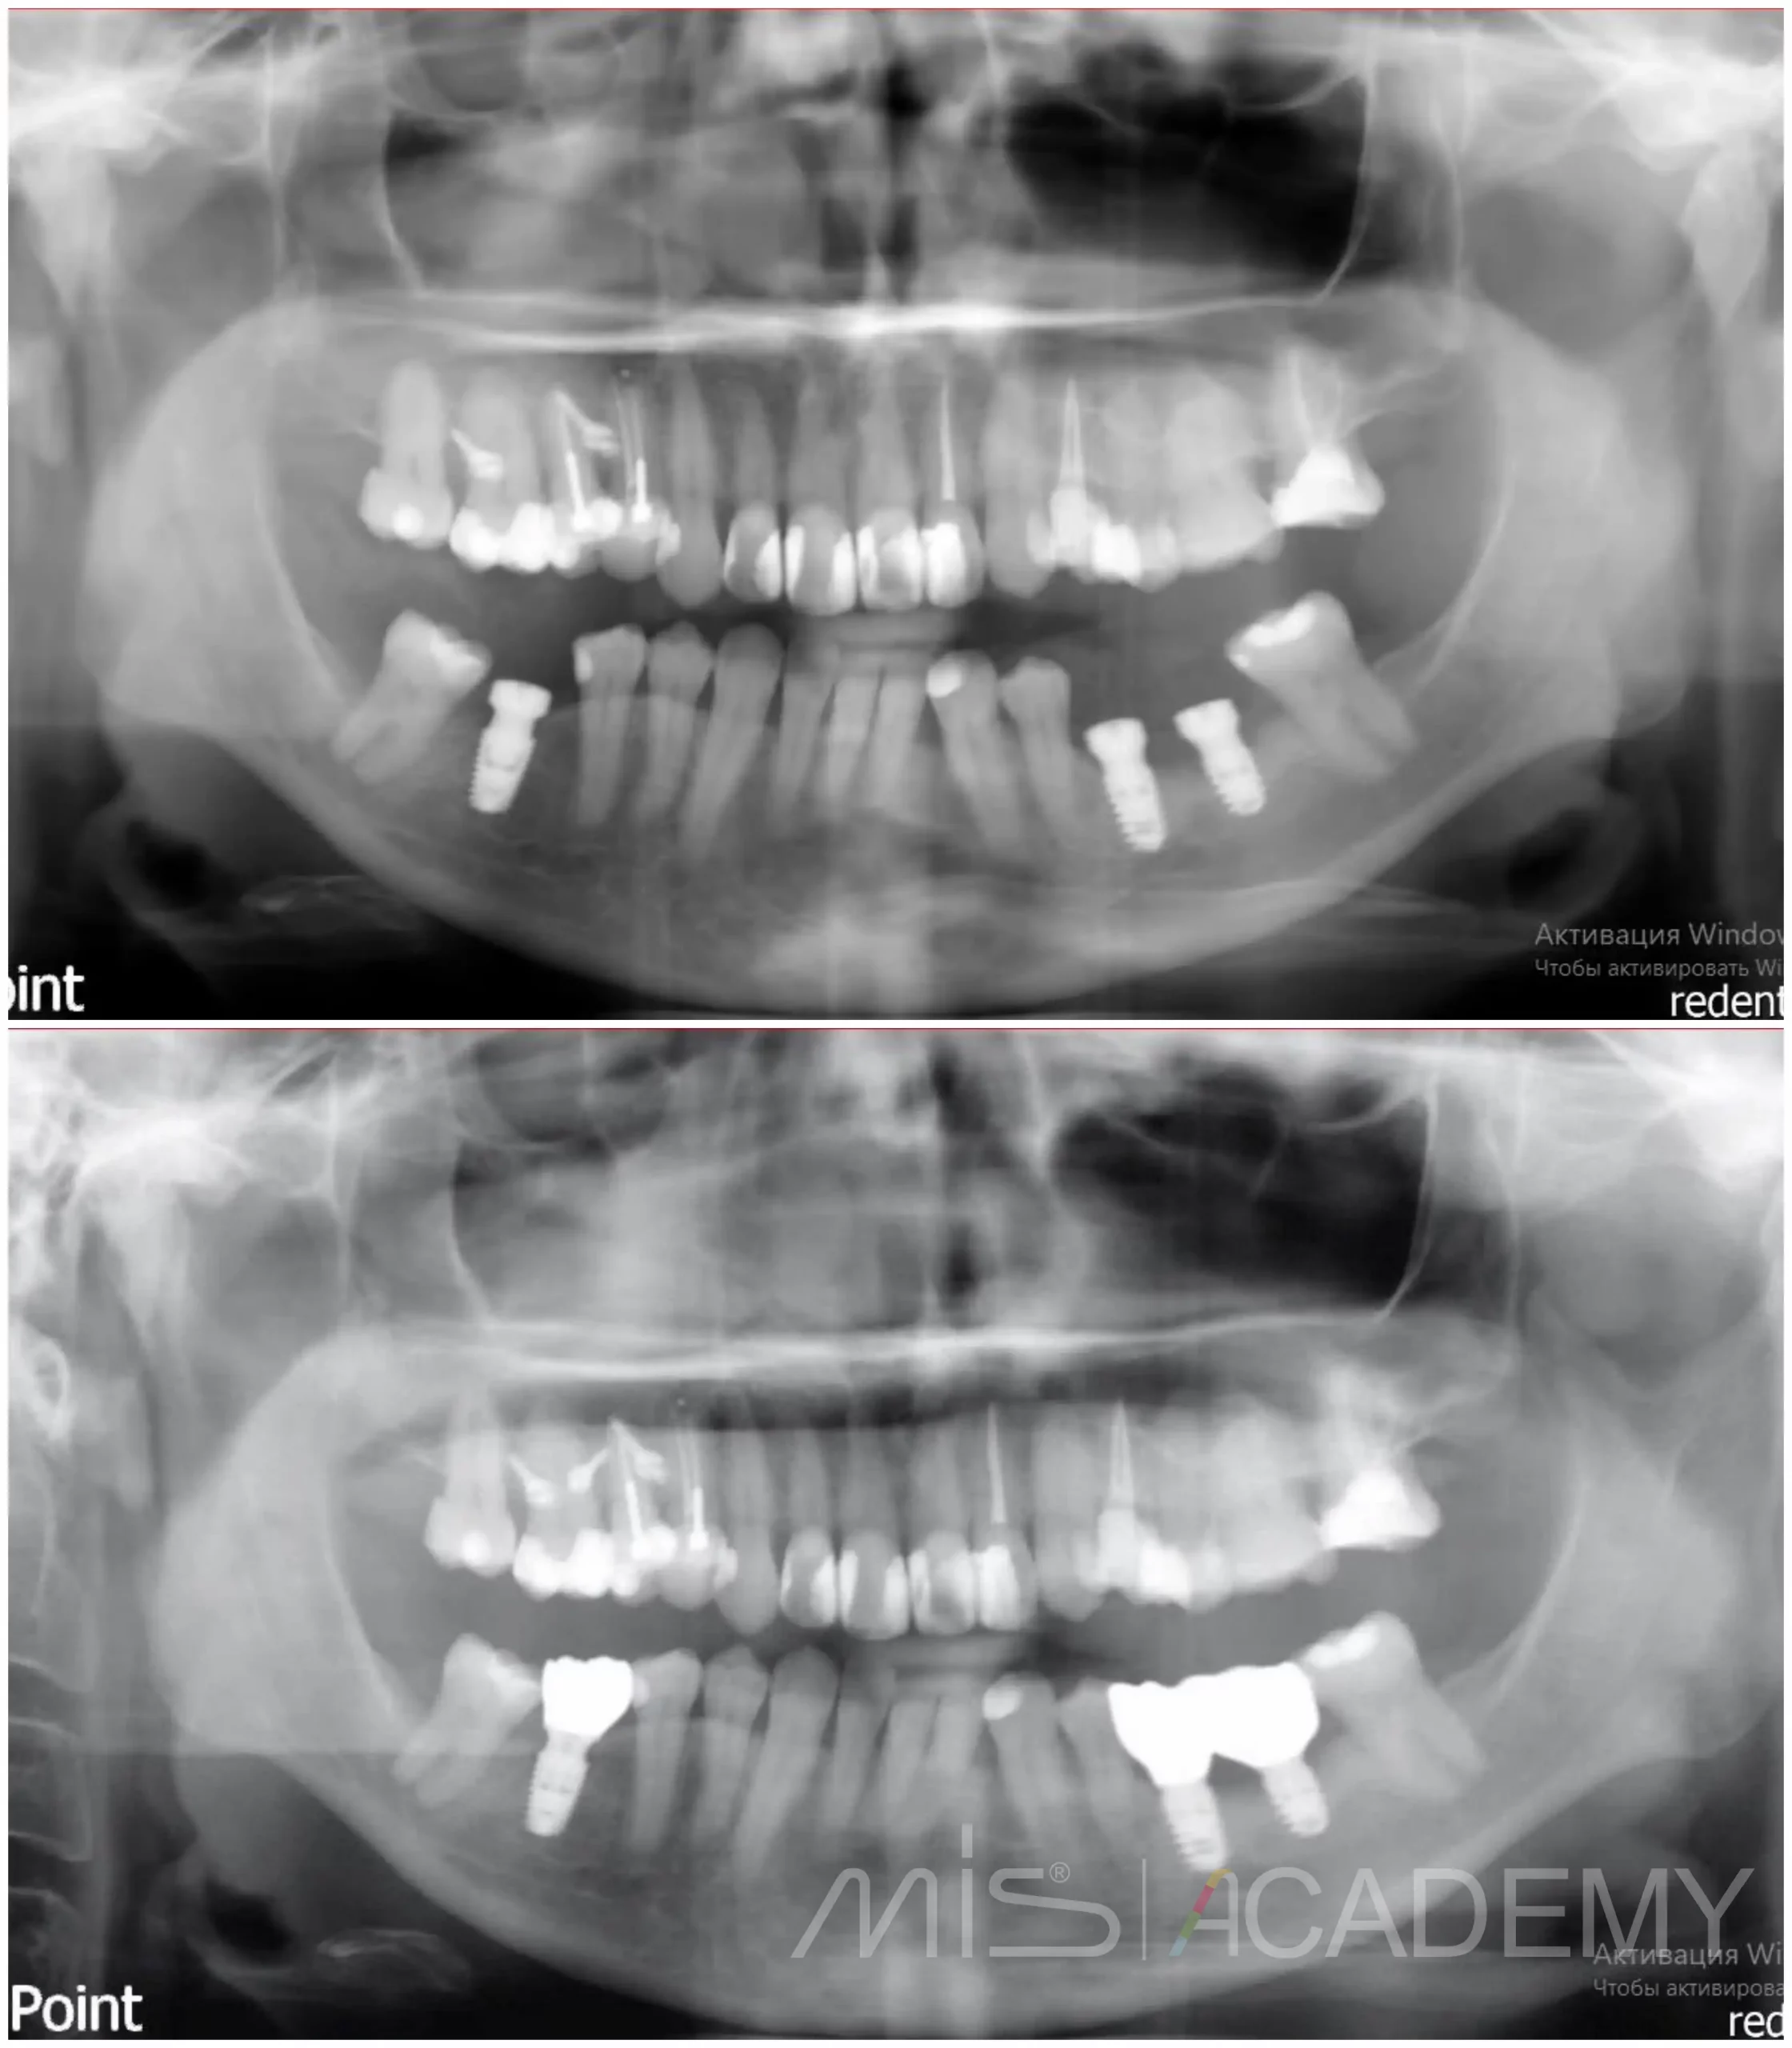

Пациент изначально обратился за костной пластикой, но после полноценного анализа данных и детального планирования мы предложили альтернативное, более рациональное решение.

— По хирургическому шаблону установили имплантаты MIS Seven высотой 8 и 6 мм.

После этого Игорь Левушкин выполнил временное, а затем и постоянное протезирование.

Хороший пример того, что не каждая клиническая ситуация требует костной пластики, иногда правильное планирование и работа с мягкими тканями дают не менее стабильный и предсказуемый результат.